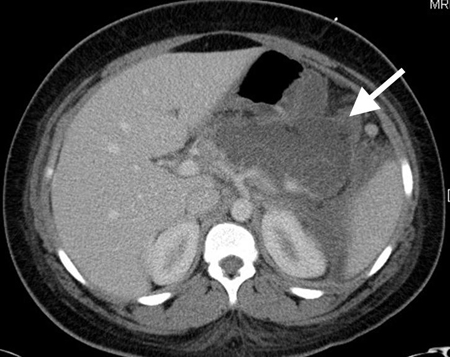

Pancreatite aguda

náuseas, vômitos, dor epigástrica que se irradia para o dorso; dor abdominal de início agudo

Exame físico

desconforto na região epigástrica ou superior do abdome; taquicardia e hipotensão em casos graves; descoloração em torno do umbigo (sinal de Cullen positivo) ou dos flancos (sinal de Grey-Turner positivo) em casos de pancreatite hemorrágica; crianças pequenas podem demonstrar apenas piora da irritabilidade e distensão abdominal

Outras investigações

- ultrassonografia abdominal:

pode parecer normal no início da evolução da doença; aumento do pâncreas; edema peripancreático; ducto pancreático dilatado; pode mostrar doença biliar subjacente

Mais - tomografia computadorizada (TC) do abdome com contraste intravenoso:

inflamação peripancreática (acúmulo de gordura); pode mostrar cálculos biliares